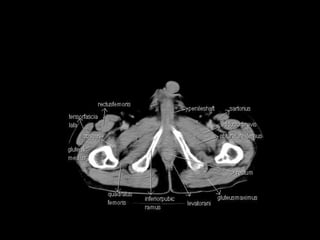

Radiographers use medical imaging equipment like X-rays and MRIs to produce images of patients' internal structures and organs. They are responsible for positioning patients, operating scanning machines, and ensuring quality images. Radiographers must have strong attention to detail, excellent communication skills, and the ability to work well under pressure to accurately capture anatomical features and diagnose any abnormalities.